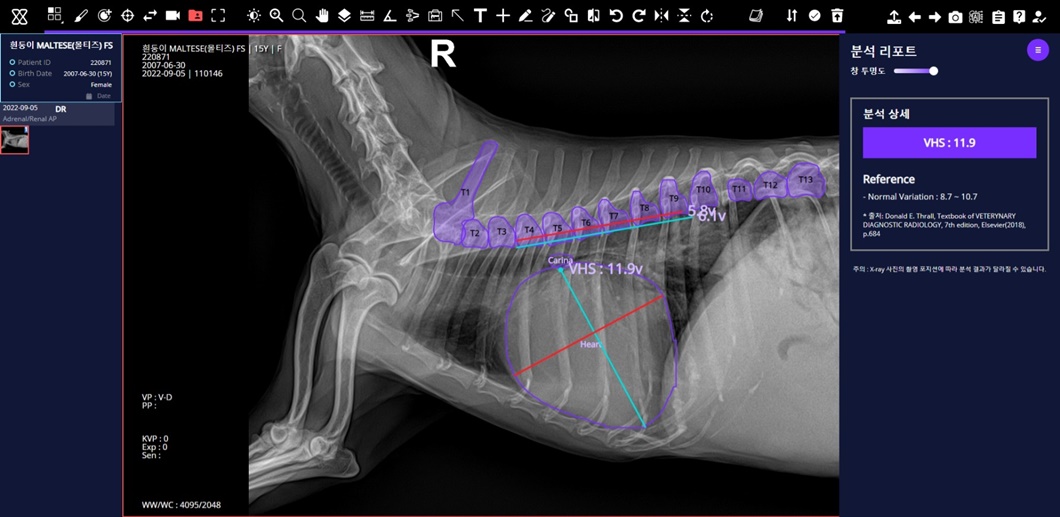

세부적으로는 ▲반려견 근골격 이상 영역 7종 검출모델 평균 질환탐지율(민감도)* 86% ▲반려견 흉부 이상 패턴 10종 분류모델 평균 질환탐지률(민감도) 84% ▲반려견 VHS(심장크기측정∙Vertebral Heart Scale) 측정모델 정확도* 97%를 기록했다.

‘엑스칼리버’를 통해 분석한 반려견의 VHS 엑스레이 사진.